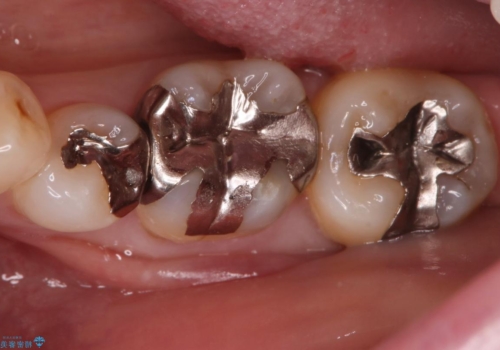

- ご友人との会話中などに、下の歯に入れてあるメタルインレーが見えてしまうのが気になり、やり変えを希望された患者様です。審美性、清掃性に優れたセラミックでの治療を希望されたため、セラミックインレー、クラウンで治療いたしました。